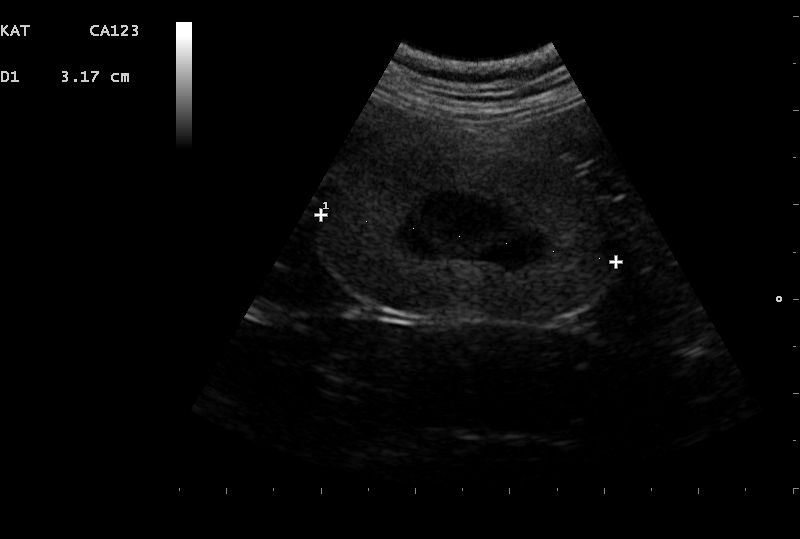

Bij chronisch nierfalen verliezen de nieren met verloop van tijd hun functie. De oorzaak is helaas vaak lastig te achterhalen maar er kan bijv. sprake zijn van een aangeboren afwijking, infectie of uitdroging. Door middel van een echo van de urinewegen kan meer informatie worden verkregen over een mogelijke oorzaak.